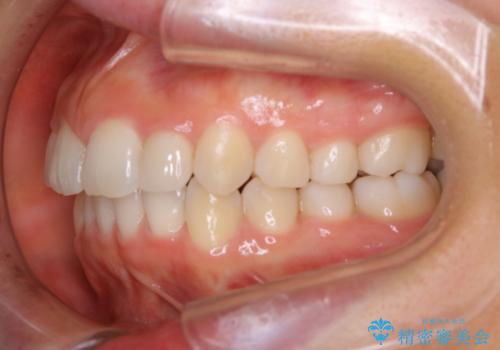

- 上の前歯が大きい事と下の前歯のがたつきを気にされてご相談にいらした方です。上の2番目の歯が矮小歯であったため、矯正治療にて歯のスペースを作った後、矮小歯には被せ物をして前歯のバランスを整えました。

歯科技工士さんとの打ち合わせを重ね、周囲の歯としっかりなじむ天然歯のような被せ物をお作りすることが出来ました。

矯正治療と補綴治療をうまく組み合わせることで、美しい口元に仕上げることが出来ました。矯正治療、補綴治療をまとめて行える総合歯科治療を体現した治療といえます。